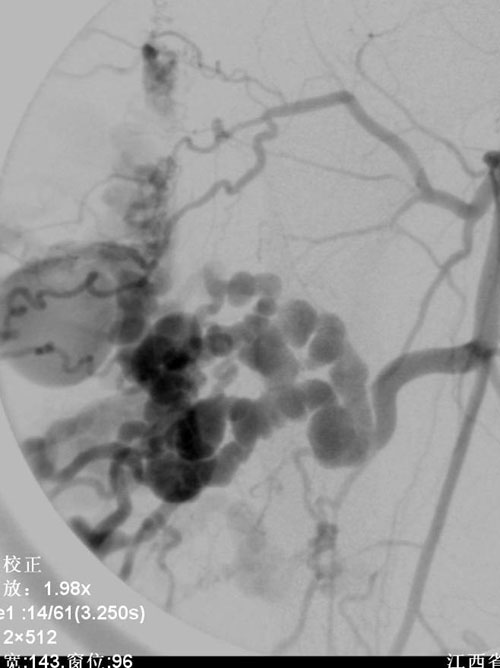

栓塞后造影

应该是下肢蔓状血管瘤用钢圈栓塞的吧.

动静脉畸形只用弹簧圈栓塞动脉主干,有效吗?侧支循环可能很好就会建立;本例靠上一支动脉也有改变,似乎没有处理,情况如何?有没有栓塞后的造影图像?

单纯用弹簧栓效果不好。

根据工作经验,这种方法处理远期疗效估计不会好,此例患者动静脉畸形为多支动脉供血,仅仅处理粗大的一只供血动脉意义不大,对于症状的缓解意义不大。应该是在末梢栓塞的基础上再加上主干栓塞。